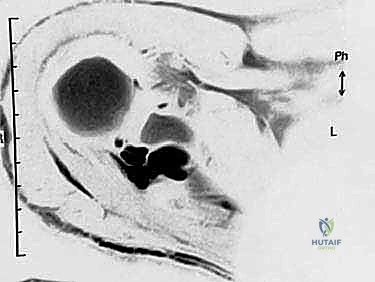

- الكيسات العقدية المجاورة للشفا (Paralabral Ganglion Cysts): تُعد هذه الكيسات من أهم وأشهر أسباب انضغاط العصب، خاصة عند الشق الشوكي الحقاني. تنشأ هذه الكيسات عادةً نتيجة تمزقات في الشفا الغضروفي (Labral Tears) لمفصل الكتف (مثل تمزقات SLAP أو تمزقات الشفا الخلفية). يعمل التمزق كصمام أحادي الاتجاه؛ يسمح للسائل الزليلي بالخروج من المفصل وتجمعه لتكوين كيسة، ولكنه يمنع عودته. مع مرور الوقت، تكبر الكيسة وتضغط بقوة على العصب.

3. التصوير بالرنين المغناطيسي (MRI)

* الكشف عن الآفات الشاغلة للحيز مثل الكيسات العقدية (Ganglion cysts) بدقة متناهية.

* تقييم حالة العضلات (هل هناك تغيرات دهنية أو ضمور لا رجعة فيه؟).

* تقييم حالة أوتار الكفة المدورة والشفا الغضروفي (لتحديد سبب تكون الكيسة إن وجدت).